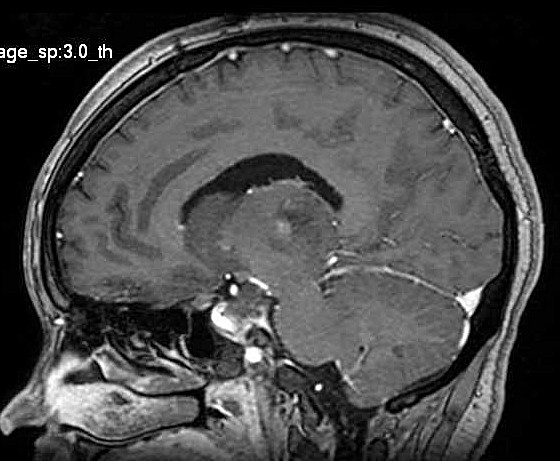

| Fem. 17a. |

| Nódulo sólido homogêneo preenchendo o III ventrículo, com limites precisos, com hipossinal em T1 e hipersinal em T2 e FLAIR, que se impregna por contraste paramagnético. Lesão menor implantada no assoalho do IV ventrículo provavelmente representa disseminação por via liquórica. |

| SAGITAIS, T1 SEM CONTRASTE | T1 COM CONTRASTE | |

| F. 17a. Tumor teratóide rabdóide atípico de III ventrículo. RM | HE | VIM, GFAP | HHF35, desmina, 1A4 | AE1AE3, EMA |